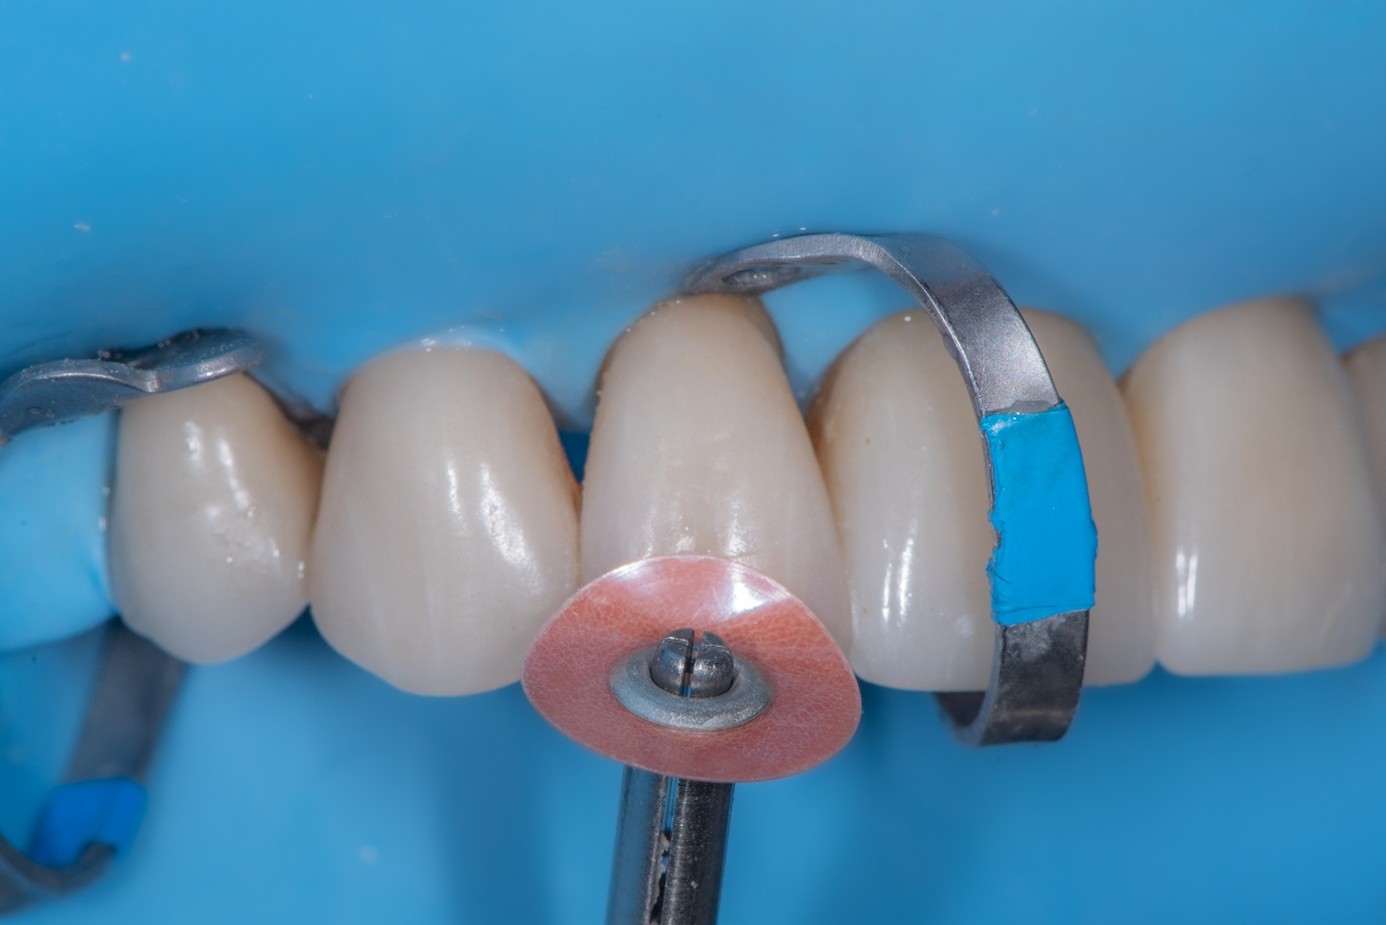

Clinical Procedure

After achieving rubber dam isolation, the fractured composite segment was first air-abraded with aluminum oxide particles to clean and roughen the surface. It was then etched with phosphoric acid for 60 seconds, rinsed, dried, and treated with silane to enhance chemical adhesion (Figure 18 through Figure 20).8,9

The tooth surface was similarly air-abraded to remove biofilm and aged resin remnants, then selectively etched with phosphoric acid. Silane was applied intraorally to the exposed composite surface to promote bonding between the old and new composite layers.10 Following this, a universal bonding agent was applied to both the tooth surface and the fractured composite segment (Figure 21 through Figure 24).

(21.) Intraoral view after rubber dam isolation, showing prepared surfaces: both sandblasted and etched, with silanization applied only to the composite surface, ready for reattachment.

Figure 21

(22.) Intraoral view after rubber dam isolation, showing prepared surfaces: both sandblasted and etched, with silanization applied only to the composite surface, ready for reattachment.

Figure 22

(23.) Intraoral view after rubber dam isolation, showing prepared surfaces: both sandblasted and etched, with silanization applied only to the composite surface, ready for reattachment.

Figure 23

(24.) Intraoral view after rubber dam isolation, showing prepared surfaces: both sandblasted and etched, with silanization applied only to the composite surface, ready for reattachment.

Figure 24